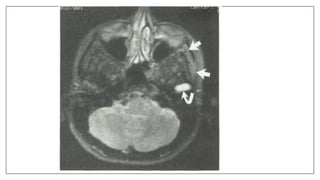

Pharyngeal recess

• Behind the ostium of the eustachian tube (ostium pharyngeum tuba

auditiva) is a deep recess, the pharyngeal recess (fossa of Rosenmüller)

• At the base of this recess is the retropharyngeal lymph node (the Node of

Rouvier.)This is clinically significant in that it may be involved in certain

head and neck cancers, notably Nasopharyngeal cancer.

L E Loh,TSG Chee, AB John.The anatomy of the Fossa of Rossenmuller- Its possible influence on